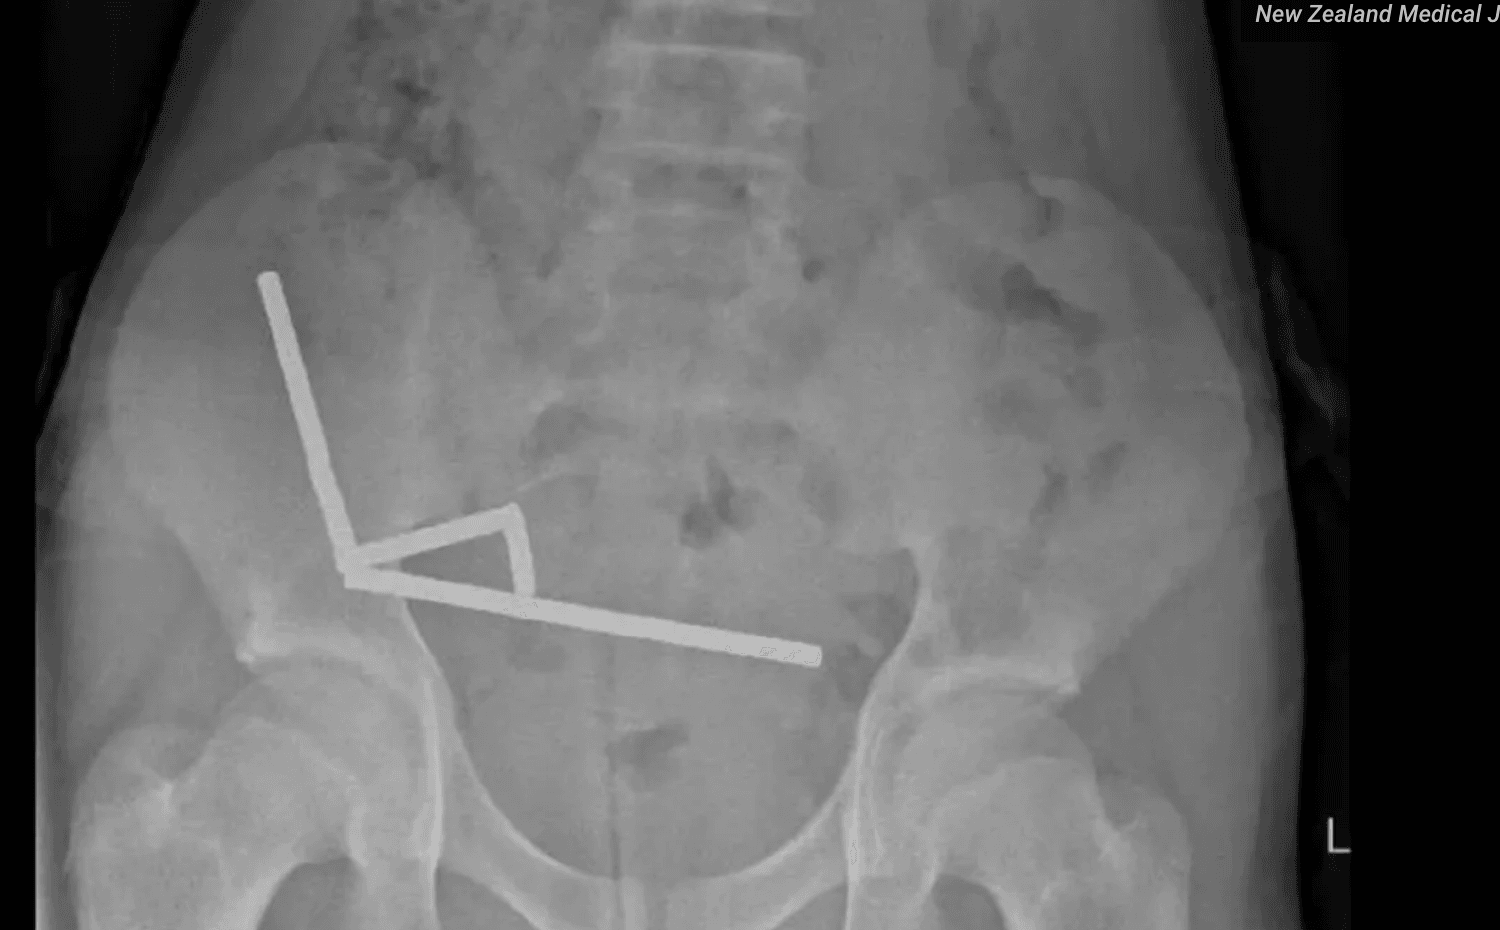

Las radiografías mostraron una imagen muy clara y muy preocupante. En el interior del intestino aparecían varias líneas de pequeñas bolitas metálicas, agrupadas y pegadas entre sí. No estaban todas en el mismo tramo, pero la fuerza magnética las hacía atraerse, aunque hubiera paredes de intestino en medio.

Esa atracción tan fuerte hizo que diferentes partes del intestino se pegaran y se comprimieran. El tejido quedó atrapado entre los imanes y perdió riego sanguíneo. Los cirujanos describieron zonas con necrosis tanto en el intestino delgado como en el ciego, que es la primera parte del intestino grueso.